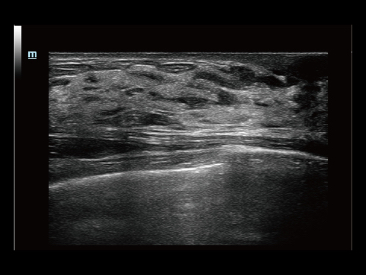

Fin dalla sua fondazione Mindray esplora continuamente nuovi modi per migliorare l'affidabilit├Ā diagnostica. Equipaggiata con la pi├╣ rivoluzionaria tecnologia ZONE Sonography?, la nuova piattaforma ZST+ di Resona 7 porta la qualit├Ā dell'immagine ecografica ad un livello superiore con l'acquisizione per zone e l'elaborazione dei dati canale.

Oltre alla qualit├Ā delle immagini di livello eccellente, Resona 7 migliora anche le capacit├Ā di ricerca clinica il rivoluzionario V Flow per la valutazione emodinamica vascolare, e l'acquisizione piani pi├╣ intelligente dal set di dati 3D per la diagnosi del sistema nervoso centrale fetale. Combinando il pi├╣ intuitivo funzionamento multi-touch basato su gesti e tutte le caratteristiche cliniche essenziali, Resona 7 sta veramente portando nuove tendenze nellŌĆÖinnovazione dellŌĆÖecografia.